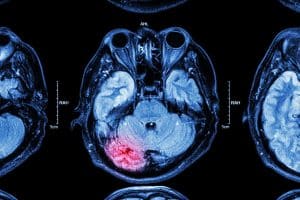

Many concussion and TBI symptoms develop or worsen over time and certain injuries might not even show up on standard imaging tests like X-rays or CT scans. As a result, some accident victims go home thinking they’re in the clear only to suffer serious and even life-threatening medical complications later on. When this happens, victims may be left with serious and long-term symptoms that come with astronomical price tags attached.